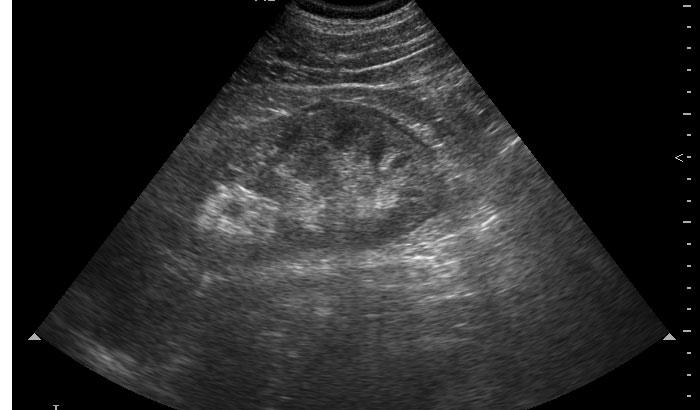

УЗИ: уретеролитиаз, уринома и нет гидронефроза

Мужчина средних лет с резкими болями в левом боку.

Возможно, очаговый пиелонефрит (участок воспалительной инфильтрации повышенной эхогенности)? Паранефрит.

по наружном контуру - жидкость, ушиб?